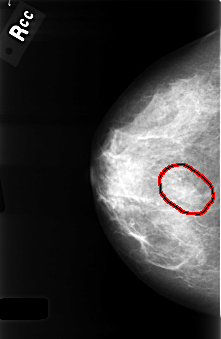

C_0334_1.RIGHT_CC

FILE: C_0334_1.RIGHT_CC.OVERLAY

TOTAL_ABNORMALITIES 1

ABNORMALITY 1

LESION_TYPE MASS SHAPE LOBULATED MARGINS OBSCURED

ASSESSMENT 4

SUBTLETY 4

PATHOLOGY BENIGN

TOTAL_OUTLINES 2

BOUNDARY